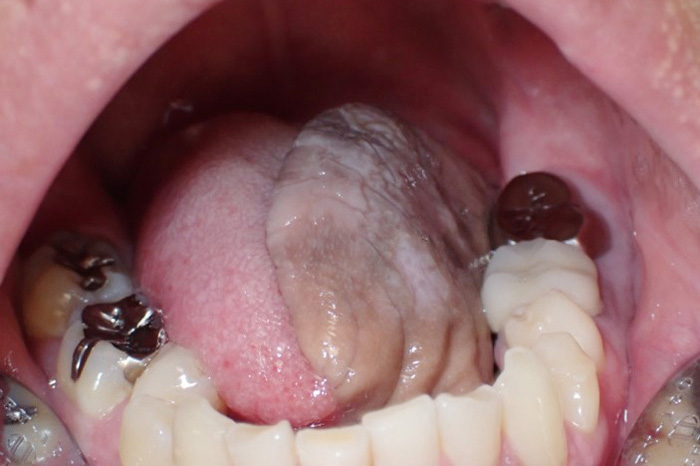

口腔腫瘍科について

令和4年から口腔腫瘍科を新たに開設させていただきました。口腔腫瘍科で主に扱う疾患は口腔がん(舌がん、歯肉がん、頬粘膜がん、口蓋がん、口底がんなど)です。また、口腔潜在的悪性疾患としての前がん病変(白板症、紅板症など)や、前がん状態(口腔扁平苔癬)なども取り扱います。治療については手術療法、化学療法、放射線療法などを疾患により組み合わせて行います。広範囲にわたる手術などは関係各科と連携・協力し適切に進めていきます。

代表画像(舌がん)

舌がん

治療後(前腕皮弁で再建)